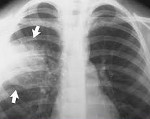

- Рентгенологического обследования органов грудной клетки в двух проекциях.

Полное диагностическое обследование при подозрении на внутрибольничную пневмонию строится на сочетании клинических, физикальных, инструментальных (рентгенография легких, КТ грудной клетки), лабораторных методов (ОАК, биохимический и газовый состав крови, бакпосев мокроты).

Для выставления соответствующего диагноза пульмонологи руководствуются рекомендуемыми критериями, включающими в себя: лихорадку выше 38,3°С, усиление бронхиальной секреции, гнойный характер мокроты или бронхиального секрета, кашель, тахипноэ, бронхиальное дыхание, влажные хрипы, инспираторную крепитацию. Факт внутрибольничной пневмонии подтверждается рентгенологическими признаками (появлением свежих инфильтратов в легочной ткани) и лабораторными данными (лейкоцитозом >12,0х109/л, палочкоядерным сдвигом >10%, артериальной гипоксемией Ра02